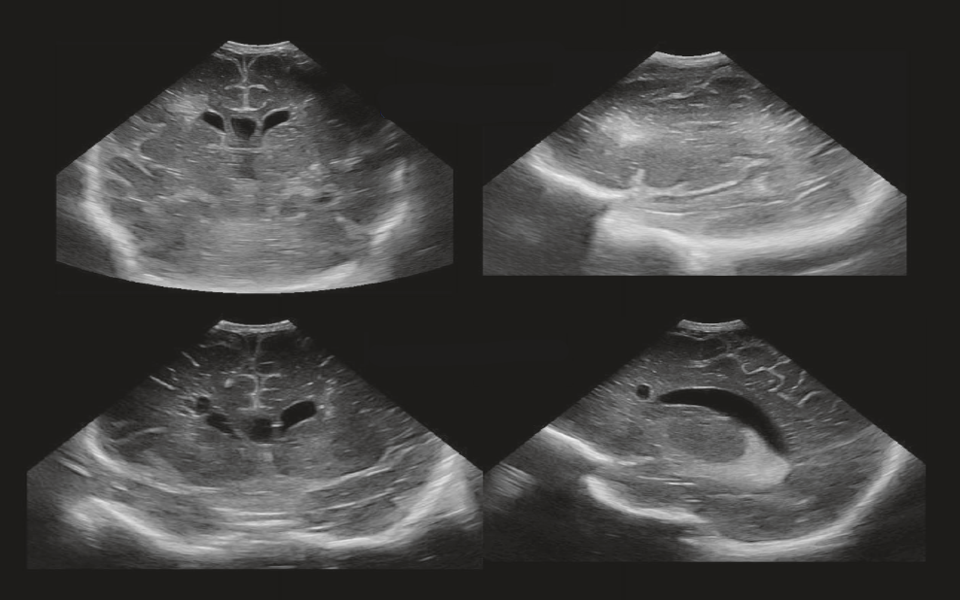

Neonatology Acute and Endstage Appearance Image